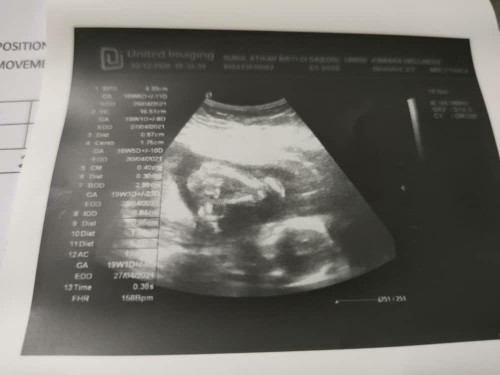

Boy OR girl

Hi sume.. sape2 pandai tengok gender ank sy ni.. ibu2 tengok gurl ke boy. 1st scan doktor ckp boy.. pastu hospital scan cakap looks like sandwich plak (girl).. ibu dh confuse..nk beli pink ke blue bju..terpksa bali unisex la agknye.. ibu and ayah excited ni.. tunggu 4tahun lbh dh ..smngt nk g cri baju..hehe.. #pregnancy #firstbaby #seriusnanya #1stimemom